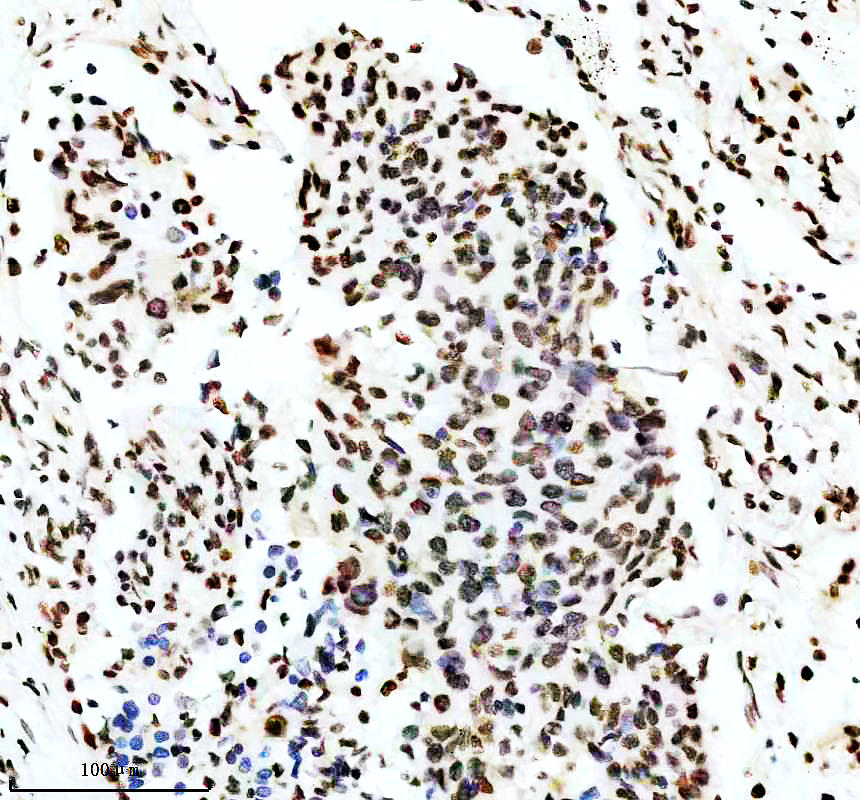

IHC analysis of P-MDM2 using anti-P-MDM2 antibody (P00054-2).

P-MDM2 was detected in a paraffin-embedded section of mouse testis tissue. The tissue section was incubated with rabbit anti-P-MDM2 Antibody (P00054-2) at a dilution of 1:200 and developed using HRP Conjugated Rabbit IgG Super Vision Assay Kit (Catalog # SV0002) with DAB (Catalog # AR1027) as the chromogen.